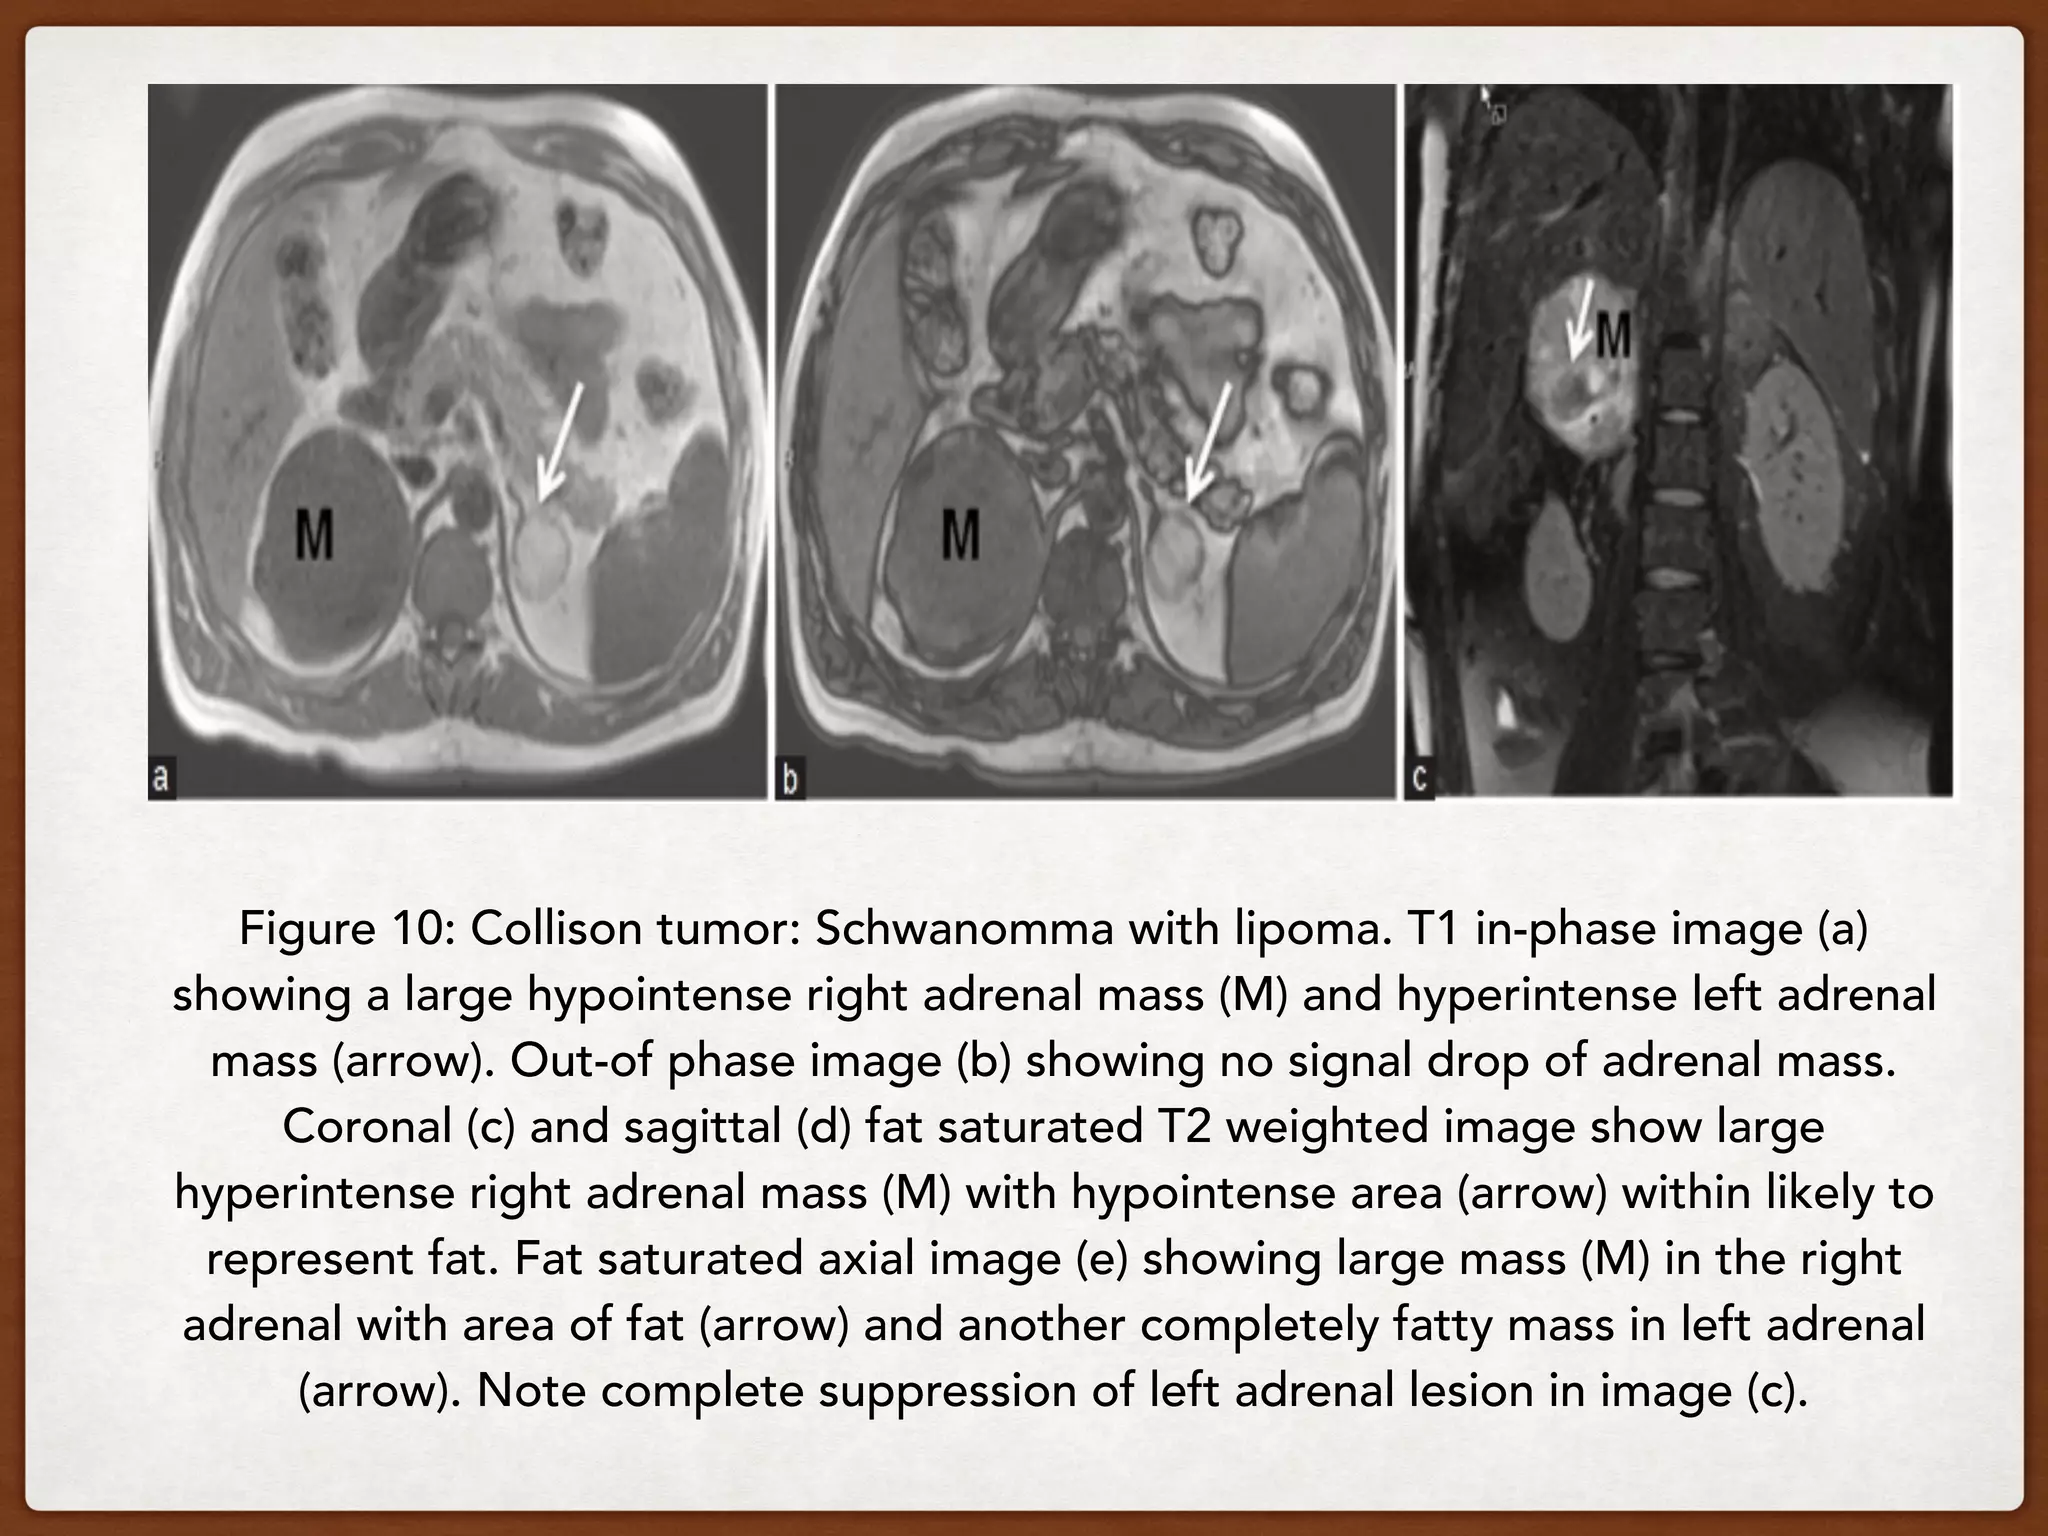

Figure 10: Collison tumor: Schwanomma with lipoma. T1 in-phase image (a)

showing a large hypointense right adrenal mass (M) and hyperintense left adrenal

mass (arrow). Out-of phase image (b) showing no signal drop of adrenal mass.

Coronal (c) and sagittal (d) fat saturated T2 weighted image show large

hyperintense right adrenal mass (M) with hypointense area (arrow) within likely to

represent fat. Fat saturated axial image (e) showing large mass (M) in the right

adrenal with area of fat (arrow) and another completely fatty mass in left adrenal

(arrow). Note complete suppression of left adrenal lesion in image (c).

Contrast enhanced image (f) shows enhancement of the right adrenal mass (M)

with nonenhancing fatty area (arrow) and complete no enhancement of left

adrenal mass (arrow). These features are suggestive of myelolipoma of right

adrenal and lipoma of left adrenal. However, at surgery the right adrenal mass

came out to be a schwanomma with separate adrenal lipoma suggesting a

collision tumor.